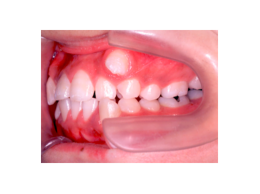

叢生 治療前 左側

いわゆる乱ぐい歯と言われていますが、八重歯もこの分類に属します。簡単に言えば、歯の大きさと顎の大きさにアンバランスがあり、並びきれないものです。形はいろいろなバリエーションがありますが、要は並びきれないので、顎を大きくするか歯を間引くかという治療方針になります。顎の骨を大きくすることもあるのですが、成長が付いて来られないとか、後戻りの危険性が大きいことなどから、歯を抜く方法が一般的です。

この患者さんでは、上下左右の歯を計4本抜きましたが、それでももスペースが足りませんので、さらに顎の形を変えて並べ替えました。

抜歯する歯は、変なところに生えていた犬歯ではなく、4番目の歯(=第一小臼歯)です。犬歯を抜くと、顎運動や歯並びの見た目、口元のふくらみがなくなることで老けて見えるなど、いろいろな悪影響があります。従って、できるだけ抜歯は避けたいのです。

歯を抜いたスペースを利用して、残りの歯をきれいに並べ替えてゆきます。この患者さんの場合は、抜いたスペースはほとんど余りませんので、意外に早く治療が終わりました。